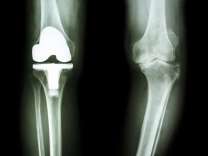

変形性膝関節症における疼痛メカニズムと保存療法の実践 ― 評価から運動療法までのリハビリ介入 ―(14日間の見逃し配信付き)

変形性膝関節症における疼痛メカニズムと保存療法の…

TKA Lab TKA Lab

エビデンスに基づいた人工膝関節置換術後の理学療法 エビデンスに基づいた人工膝関節置換術後の理学療法